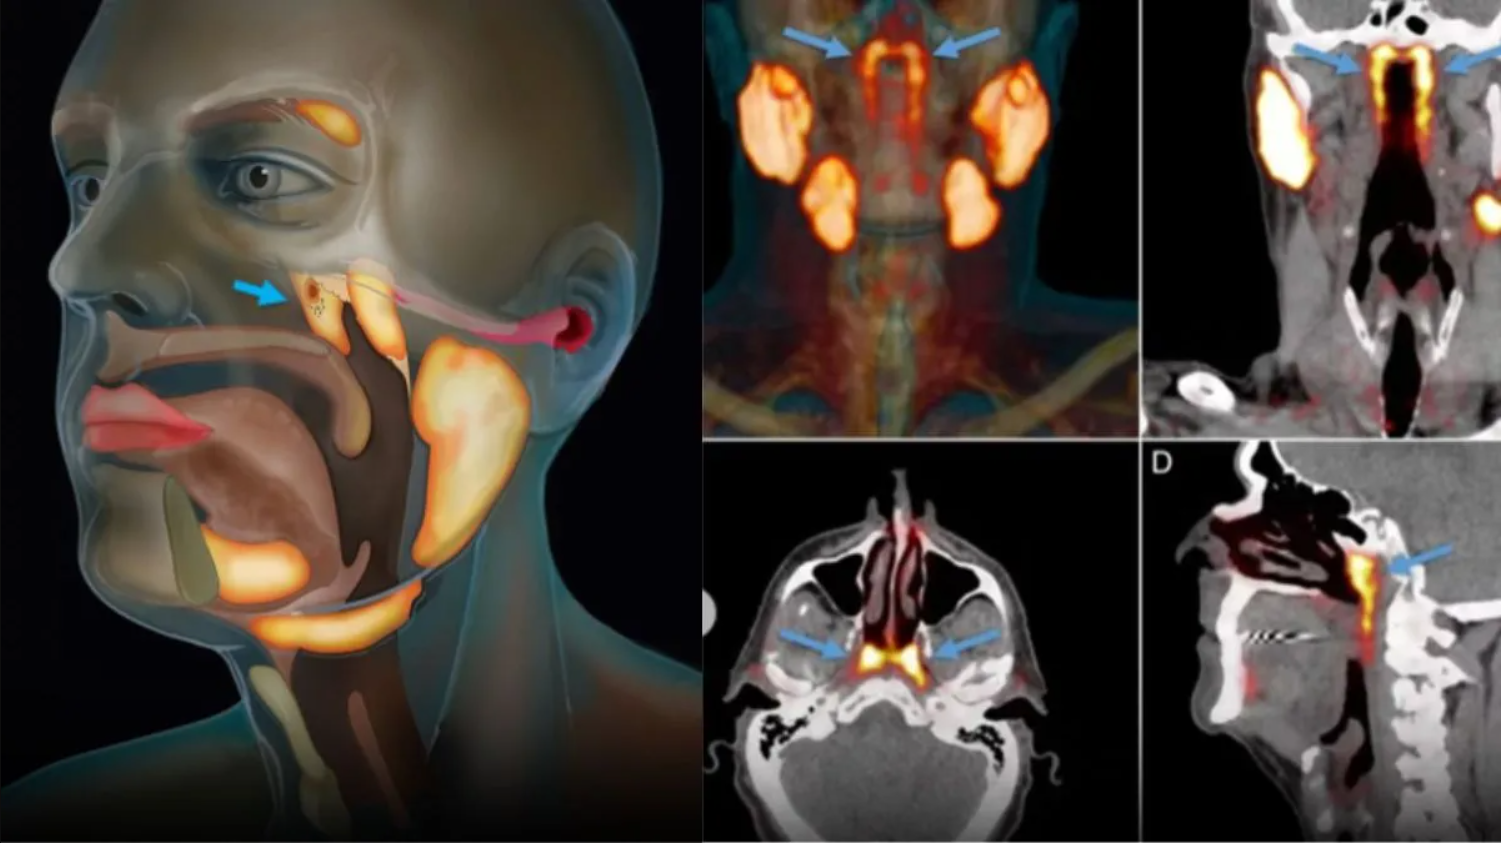

Theo PubMed, vào năm 2020, các nhà nghiên cứu Hà Lan công bố phát hiện một cặp tuyến nước bọt mới nằm ngay phía sau mũi, trong khu vực nối giữa khoang mũi và họng. Sau đó, nó đã được các chuyên gia đặt tên là tuyến nước bọt ống hầu (tubarial salivary glands). Phát hiện này lập tức làm dậy sóng truyền thông và cộng đồng khoa học vì nếu đúng, nó sẽ bổ sung vào "bản đồ" giải phẫu người vốn tự hào có 3 cặp tuyến nước bọt lớn đã được biết đến lâu nay.

Các nhà nghiên cứu Hà Lan công bố phát hiện cơ quan mới mới nằm ngay phía sau mũi, trong khu vực nối giữa khoang mũi và họng. (Ảnh: Utoronto)

Theo NKI, câu chuyện bắt đầu không phải từ phòng mổ giải phẫu mà từ… máy PET/CT cho bệnh nhân ung thư tiền liệt tuyến. Khi các bác sĩ tiêm chất đánh dấu và soi hình ảnh, họ thấy hai vùng sáng bất thường ở vòm họng xuất hiện nhất quán trong hàng loạt bệnh nhân đã gợi ý có một cấu trúc tuyến lớn hơn những "tuyến nhỏ rải rác" mà sách y đã mô tả trước đó. Khám nghiệm thêm trên xác và phân tích mô cho thấy tồn tại mô tuyến với nhiều ống dẫn, đủ để các tác giả đặt vấn đề đây là một "vùng tuyến" có thể coi là cơ quan.